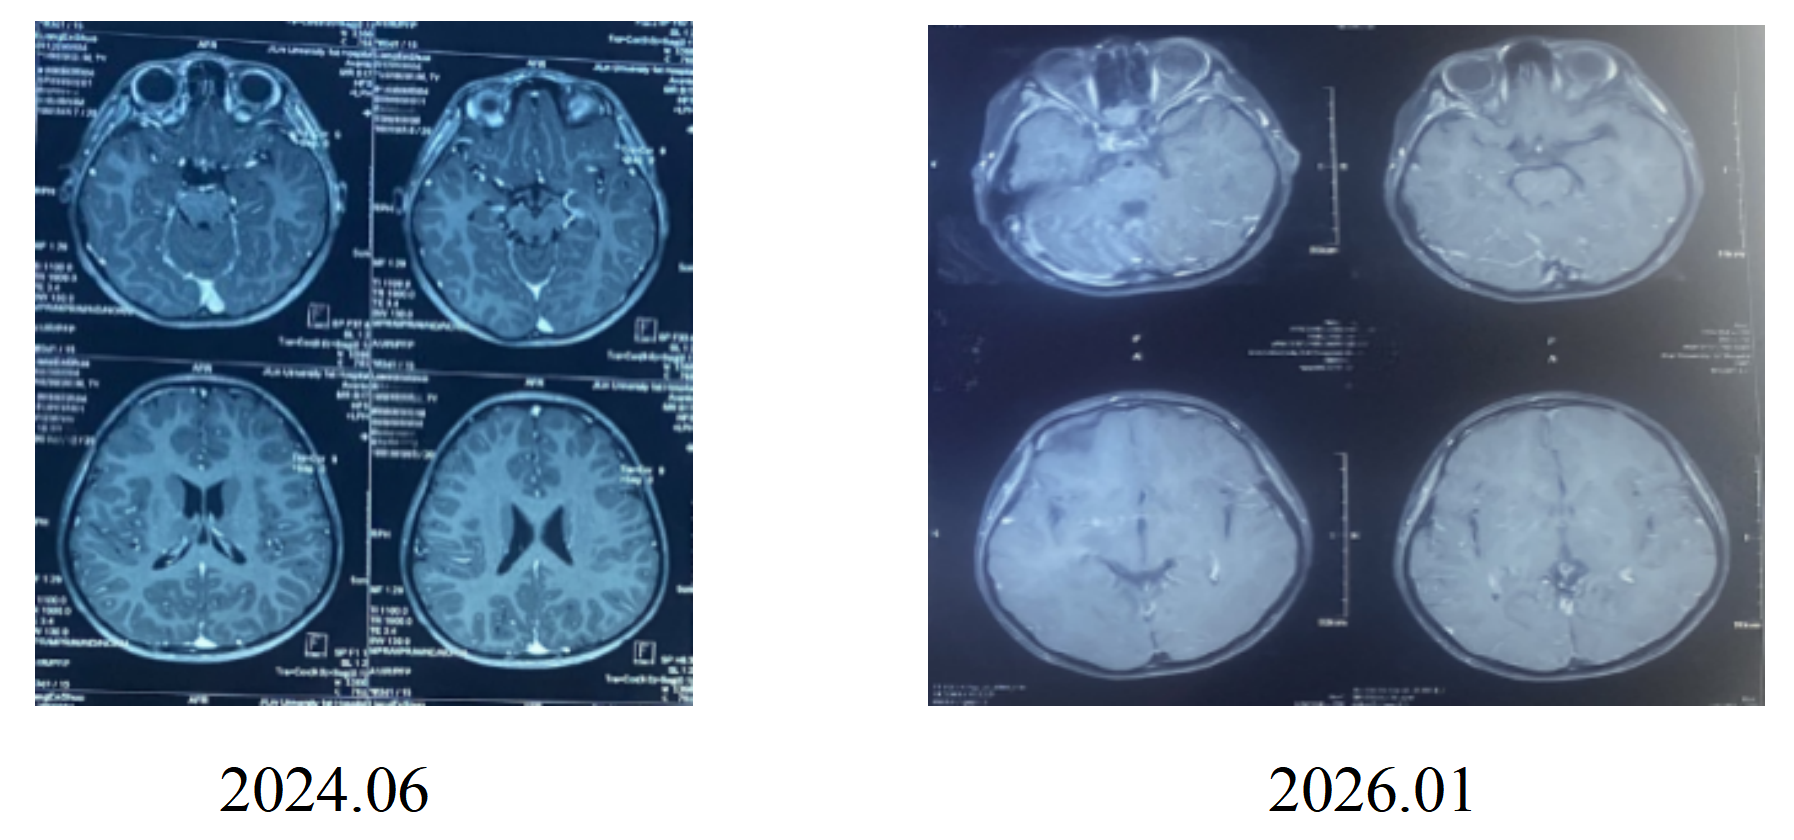

头部MRI增强(2024.06、2026.01):

未见明显异常。